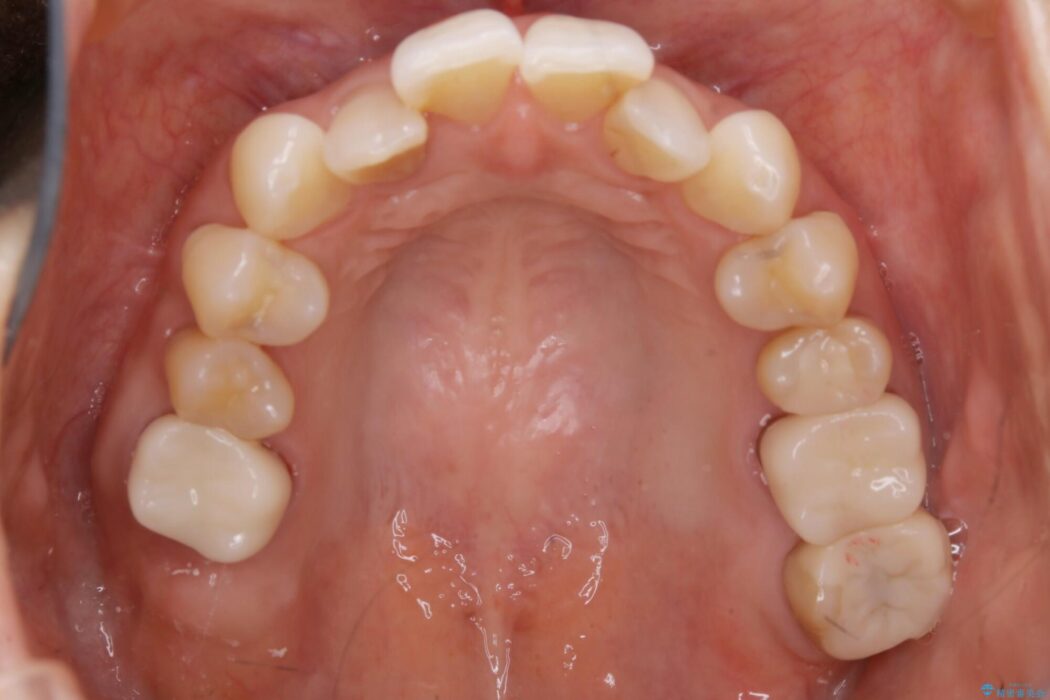

歯列弓全体の形状を整えるとともに歯の大きさもコントロールすることで非抜歯にて矯正を行いました。

気になっていたガタつきも改善され、患者様にはご満足いただけました。

歯列弓の拡大

歯並びが悪くなる原因の一つに「歯列弓の狭窄」というものがあります。

奥歯や前歯が内側(舌側)に倒れ込んでしまったり、歯が生えてくる位置が内側になってしまうことにより歯並びのアーチが狭くなってしまうことを言います。

このような場合、歯並びのアーチを拡大してあげるだけでもガタつきを無くすためのスペースがかなり作れることがあります。